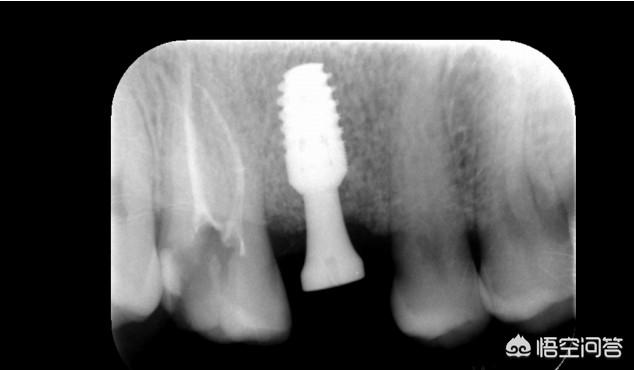

种植牙前期先给牙槽骨植入一颗植体,等植体和牙槽骨愈合后(大概3-6个月)再安装调试基台和牙冠。就算完成。期间可佩戴临时牙冠方便吃东西。